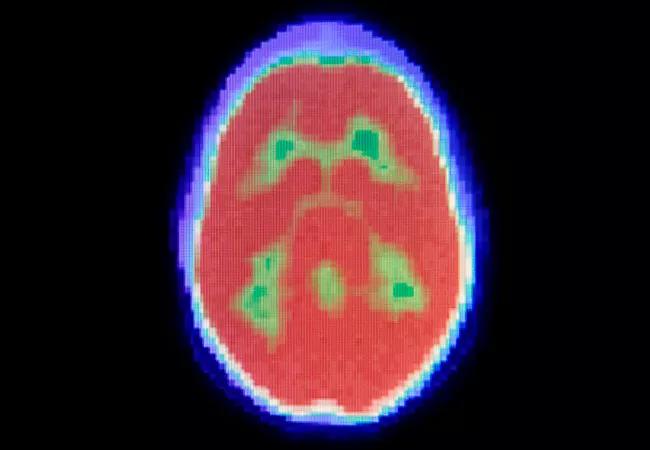

The feasibility of using 18F-clofarabine as a diagnostic imaging tracer to measure deoxycytidine kinase (DCK) activity in solid tumors and their metastases is being explored in a pilot study being conducted at Cleveland Clinic. Currently, no positron emission tomography (PET) imaging agent in routine use measures the activity and function of tumor intrinsic pyrimidine metabolism, which is critical to determine the clinical activity of several mainstay cancer therapies.

“The purpose of the pilot study is to evaluate feasibility and the biodistribution of clofarabine as a radiotracer,” says Omar Mian, MD, PhD, radiation oncologist at Cleveland Clinic and principal investigator of the pilot study. “We’re asking, is the radiotracer being taken up by tumors and lighting them up without causing significant side effects?”

Though the initial pilot will evaluate feasibility and safety, ultimately, the investigators’ goal is to determine whether PET imaging using microdoses of 18F-clofarabine can localize a patient’s cancer and predict responsiveness to DCK-dependent anticancer drugs such as gemcitabine, says Dr. Mian.

“Clofarabine is enriched in tumor cells that upregulate DCK,” Dr. Mian says. “Response to a number of standard chemotherapies such as gemcitabine, fluorouracil and cytarabine depends on expression levels of DCK that would increase the tumor’s uptake of clofarabine as a radiotracer.”

Ruling out candidates for DCK-dependent chemotherapies when tumors have no uptake of 18F-clofarabine would avoid exposing patients to toxicities while permitting selection of potentially more effective alternate first-line therapies, rather than waiting for failure of standard therapies, says co-investigator Zhenghong Lee, PhD, professor at Case Western Reserve University. The imaging agent is applied at a subtherapeutic dose to probe DCK status. “If the enzyme is active, it’s more likely that the cancer will respond to standard treatment because it is of the same family as the radiotracer,” he says.